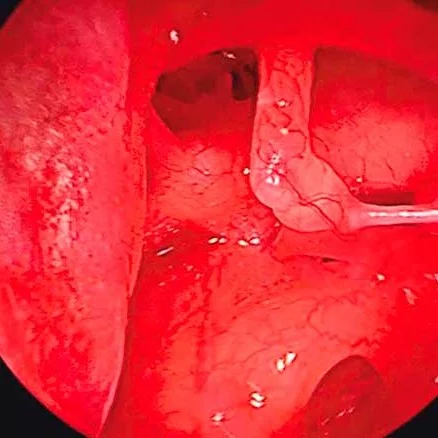

La otosclerosis está causada por un crecimiento anormal del hueso en el oído medio, lo cual desemboca en una pérdida auditiva. Es una patología crónica que provoca esponjosidad en los huesos y la fijación de la base del estribo en la ventana oval.